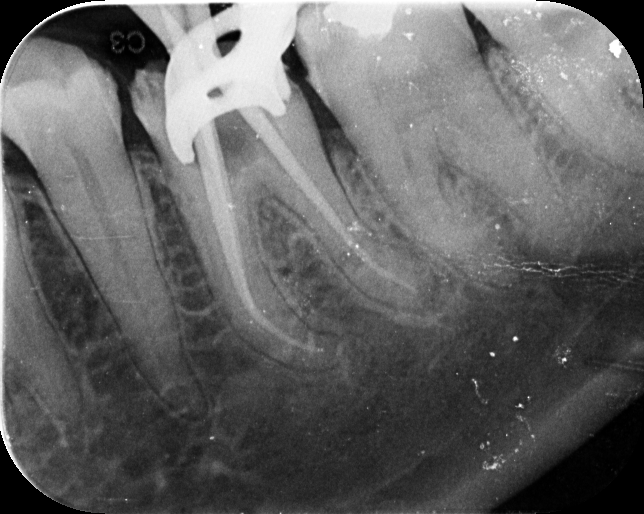

Our treatments are performed using advanced dental microscopes that magnify up to 25x- allowing us to identify previously hidden canals, fractures, or infected areas that standard tools may miss. This level of detail means faster, more accurate procedures and fewer surprises, giving your tooth the attention it truly deserves.

We streamline the retreatment process by using enhanced imaging, digital diagnostics, and precision tools-reducing unnecessary visits and helping you get back to normal faster.